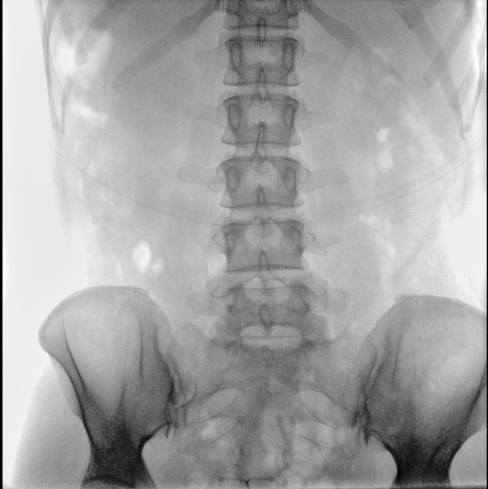

臨床應(yīng)用廣泛,適用于關(guān)節(jié)手術(shù)、創(chuàng)傷手術(shù)、脊柱手術(shù)、疼痛治療等。

●屏幕內(nèi)置DICOM醫(yī)學(xué)曲線,幫助辨認(rèn)細(xì)微組織的密度變化。

●27英寸大尺寸顯示器,更大視野,方便觀察微小結(jié)構(gòu)。

●一屏雙顯,可同時觀察正側(cè)位圖像,便于對比觀察。